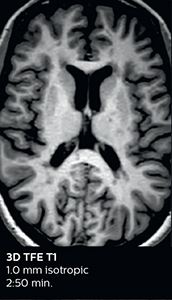

According to Dr. Savatovsky, Ingenia Elition has an impact in virtually all examinations. “We can either make the scanning faster compared to our older Ingenia 3.0T, or we save enough time so that we can add sequences we wouldn’t perform otherwise, or increase resolution. So, I think it has benefits for most of our patients.” “Some routine exams that we use every day have been shortened since we started using Elition. For example, we now use mostly a comprehensive stroke protocol (high b-value diffusion, fast 3D FLAIR, TOF, supra-aortic vessels angiography, SWIp, T1 post gad) that lasts 10 to 11 minutes, but our fast stroke protocol takes only 7 minutes. Our routine IAC needs about 10 minutes scan time and our comprehensive brain MS examination requires no longer than 13 minutes of scan time. Our ability to reduce acquisition times of most sequences helps to shorten total examination times, which in turn helps us to increase the number of patients we scan per day. “The main breakthrough for us was that Compressed SENSE and Multiband SENSE have allowed us to accelerate our examinations. Alternatively, we can invest the time gained in obtaining higher spatial resolution to see more details, or we can add additional sequences,” says Dr. Savatovsky. “That’s a big improvement from what we did before.”

A two year follow-up scan of a CPA meningioma using both Ingenia 3.0T without CS and Ingenia Elition 3.0T with Compressed SENSE allows for a nice comparison to demonstrate the protocol improvements achieved on the Elition: 3D FLAIR has a shortened scan time, improved SNR and still the same spatial resolution. BrainView (3D T1 TSE) has improved spatial resolution and SNR with shortened scan time. For 3D T2 Drive the spatial resolution has been improved. 3D THRIVE used to have an interpolated 0.8 mm slice thickness, but true thickness at 1.6 mm, so that axial slices displayed a decent quality, but reformats were suboptimal. Compressed SENSE is used on Elition to improve spatial resolution and reduce the non-interpolated slice thickness to allow smoothly reformatted images. Total scan time (adding SmartBrain and an additional b2000 diffusion) was 13:19 on Ingenia, and is now reduced to 10:42 on Ingenia Elition.

Ingenia 3.0T (without Compressed SENSE)

3D FLAIR 1.0 x 1.0 x 1.0 mm* 4:24 min.

3D TSE T1w 1.0 x 1.0 x 1.2 mm* 2:40 min.

3D T2w Drive 0.8 x 0.8 x 1.0 mm* 3:05 min.

3D T1w THRIVE 0.8 x 0.8 x 1.6 mm* 1:30 min.

Ingenia Elition 3.0T with Compressed SENSE

3D FLAIR 1.0 x 1.0 x 1.0 mm* 2:50 min.

3D TSE T1w 1.0 x 1.0 x 1.0 mm* 2:10 min.

3D T2w Drive 0.7 x 0.7 x 0.7 mm* 2:52 min.

3D T1w THRIVE 0.7 x 0.7 x 0.8 mm* 1:30 min.

*true voxel size, without interpolation